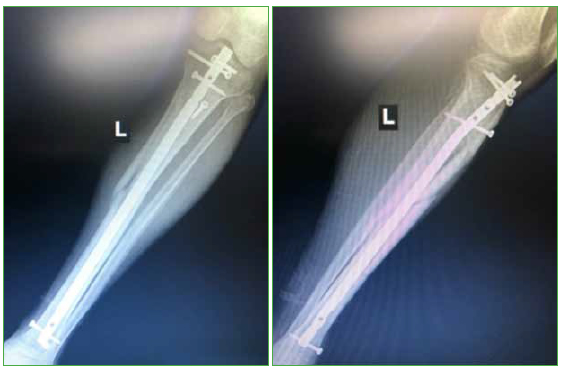

Tratamiento con clavo endomedular de las fracturas metafisarias proximales y distales de tibia. Abordaje pararrotuliano medial en posición de semiextensión